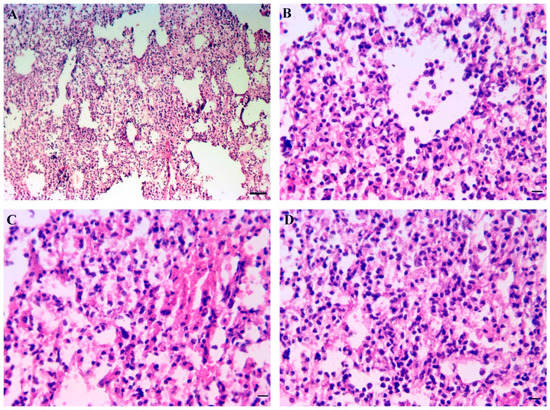

3.9. Inner Organs Histopathology